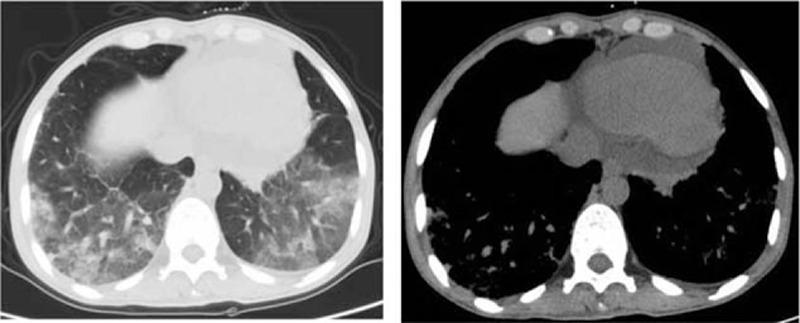

Hypereosinophilic syndrome (HES) can be fatal, particularly when eosinophils infiltrate vital organs and/or if extensive thrombosis develops. However there are no standard recommendations for the use of anticoagulant therapy of HES in the setting of thrombosis.

METHODS

We herein present a case of a 46-year-old female who presented with marked peripheral eosinophilia with symptoms of multi-organ infiltration and extensive deep venous thrombosis (DVT). In this case, evaluation was carried out before the diagnosis was established, and timely standard-dose corticosteroids combined with a new oral anticoagulant (NOAC) therapy were carried out.